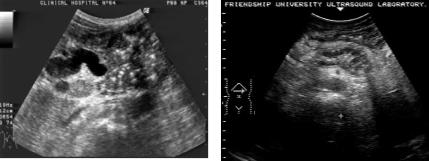

Рис. 55. Ультразвуковые томограммы при хроническом панкреатите:

а- кальцинаты в области головки поджелудочной железы;

б- панкретикоэктазия